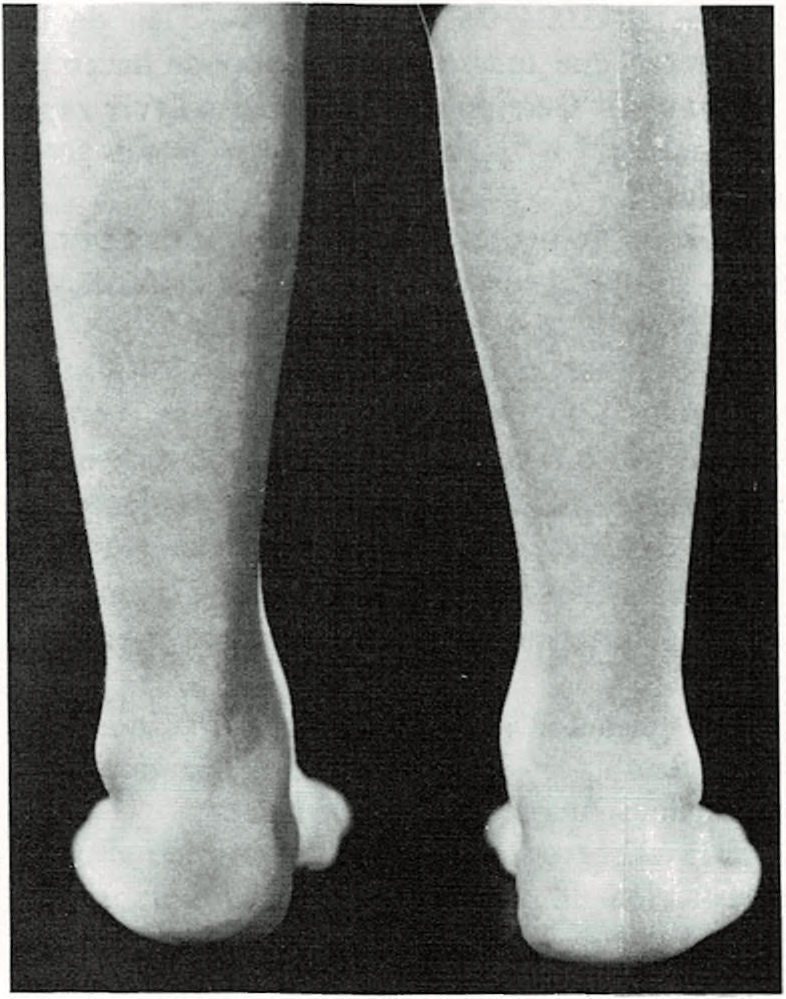

Piernas arqueadas.

Casi todos los recién nacidos parecen tener las piernas curvas. Las rodillas

se hallan dirigidas hacia fuera y los pies ligeramente vueltos hacia dentro. A pesar de que los huesos generalmente están bien formados, las piernas tienden a seguir adoptando la posición que tenían en el claustro materno.

Las piernas curvas no desaparecen en el niño hasta al cabo de un cierto tiempo de caminar. Deben enderezarse primero el tobillo y los músculos del pie, así como los músculos y ligamentos de sus piernas y rodillas. A medida que los músculos se fortalecen al andar, las piernas van apareciendo más rectas y las rodillas más juntas. La edad media en la cual desaparece la incurvación de las piernas es entre 1 y 2 años.

Si tiene las piernas excesivamente incurvadas o si a los dos años no se han enderezado, se consultará al médico.

En algunos casos, las piernas incurvadas pueden estar provocadas por un raquitismo, producido por deficiencia alimenticia de vitamina D. Sólo raramente será necesario un tratamiento especial con ortopedia o cirugía.